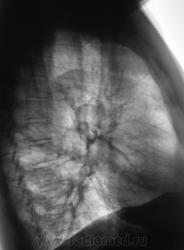

Первый срез.

Второй срез.

Более вероятна бронхо-легочная киста

Для гипоплазии артерия должна быть недоразвитой. А на томограммах нормальных размеров и диаметра артерия огибает некую овальую зону. Все-таки скорее киста, уважаемый Валентин Львович.

На мой взгляд, В.Г. прав. Похоже на прогрессирующую легочную дистрофию.

Складывается впечатление об отсутствии межолевых борозд...что наверное косвено может свидетельствовать об аномалии развития..